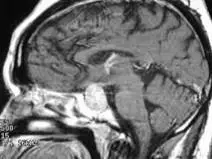

40 歲男性病患發現有兩側顳葉偏盲( bitemporal hemianopsia )症狀,泌乳激素值為 49 ng/mL (prolactin level of 49 ng/mL ),磁振造影檢查( MRI )如下列圖示,對此病灶最佳治療選擇為何?

本題 MRI 為矢狀切面 T1 加權影像,可見下列典型特徵:

- 腫瘤位置與大小:蝶鞍區(sellar region)可見一等訊號至略低訊號腫塊,伴有明顯向鞍上延伸(suprasellar extension),腫瘤直徑超過 1 cm,符合大腺瘤(macroadenoma)定義(直徑 ≥ 10 mm)。

- 視交叉壓迫(optic chiasm compression):腫瘤向上推擠,符合臨床呈現的兩側顳側偏盲(bitemporal hemianopsia)——視交叉中央交叉纖維受壓,導致兩眼顳側視野缺損。

- 腦結構影響:腫瘤佔據鞍上空間,正常垂體結構難以辨識,未見腦室擴大,無腦積水表現。

- 臨床意義:腫瘤大小加上視交叉壓迫,代表病灶具有顯著佔位效應(mass effect),視覺系統已受到器質性損害。